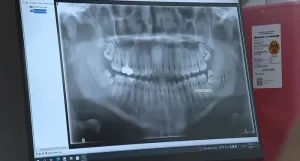

Seventeen-year-old Dante Scott, facing the removal of his four wisdom teeth, is receiving this $5,000 procedure for free, thanks to Westwood Oral Surgery’s new “Wisdom